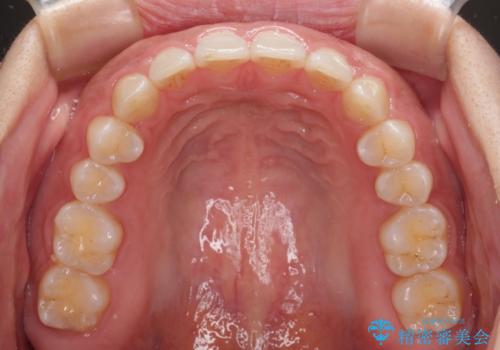

【モニター】ディープバイトを治す ワイヤー装置による矯正治療

手前に傾斜している奥歯を直立させながら、歯列全体の平面を均一に整えることでディープバイトを改善していくこととしました。

ディープバイトは咬合力が強いことが特徴であり、より良い仕上がりとするために、臼歯部のコントロールを行いやすいワイヤー装置を用いて矯正治療を行うこととしました。

ディープバイトが改善されたことで、食いしばりしかできなかった状態からスムーズな歯ぎしりができるようになりました。